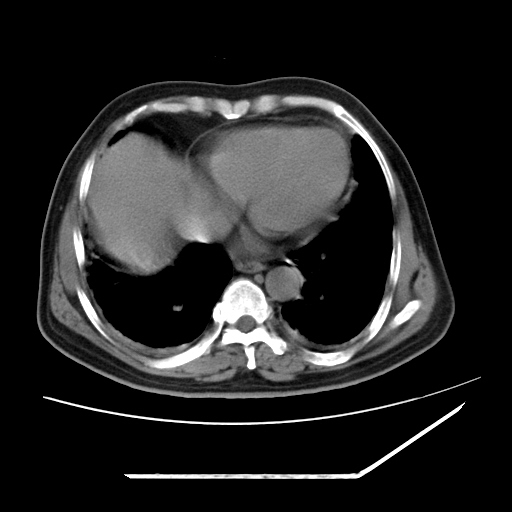

男,57,畏寒,发热

1)考虑两肺感染性病变(金黄色葡萄球菌肺炎?);建议抗炎治疗后复查排除其他。2)双侧少量胸腔积液。

两肺野多发大小不一高密度灶,纵膈内见肿大淋巴结,要考虑转移瘤可能。双侧胸腔少量积液。